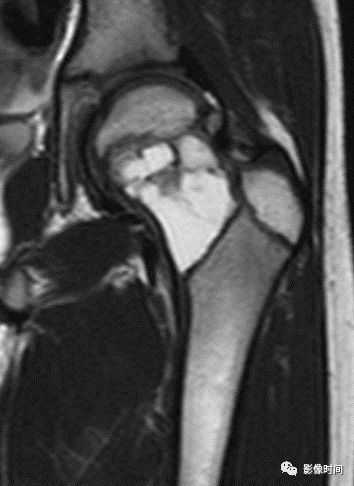

(二)瘤软骨  为肿瘤细胞产生的软骨基质,多来源于软骨类肿瘤,或内有化生瘤软骨成分的其他肿瘤如成软骨型骨肉瘤。瘤软骨为软组织密度,未钙化时,主要通过 MRI 检查显示。

由于瘤软骨多由富含水分及粘多糖的透明软骨构成,故 T1WI 呈偏低信号,T2WI 或 PDWI 呈明显高信号,被低信号的纤维间隔分开呈分叶状(图 24、图 25a-b),增强扫描多呈不均匀分隔状强化(图 25c),主要是纤维间隔强化,瘤软骨强化不明显之故。

图 24  瘤软骨:内生软骨瘤

图 25  瘤软骨:内生软骨瘤